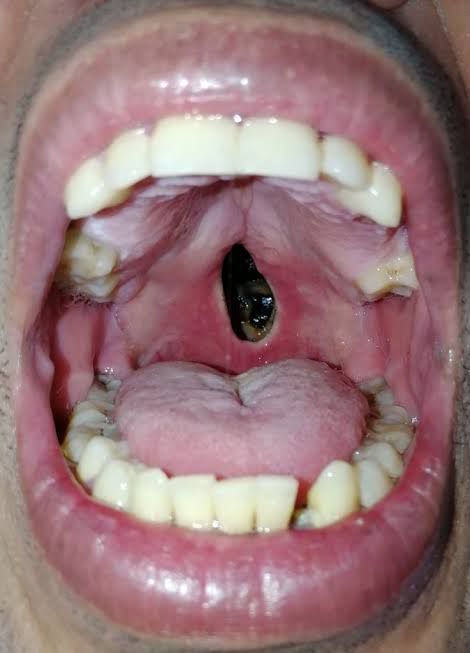

Очень часто у употребляющих снижено понятие боли, поэтому зубы могут быть в очень плохом состоянии. То есть они могут либо отсутствовать, от них остаются чёрные корешки, могут быть обломаны, стерты. Часто шейки могут быть от темно-коричневого до черного цвета, крошится просто на глазах. Покрыты огромным количеством зубного налета, камнями. При этом ни один из симптомов может не доставлять боли, а лишь эстетический дискомфорт.

3. Как уже говорилось ранее, частный врач. Цены дешевле, тк его не волнует работа админа, склада, количество воды, электричества и прочего. Цены устанавливает сам, ниже рынка. Если зубы совсем в плохом состоянии, то вариант удалить все, ставить имплантаты и на них новые зубами - это хороший вариант, и у частного врача будут норм цены.